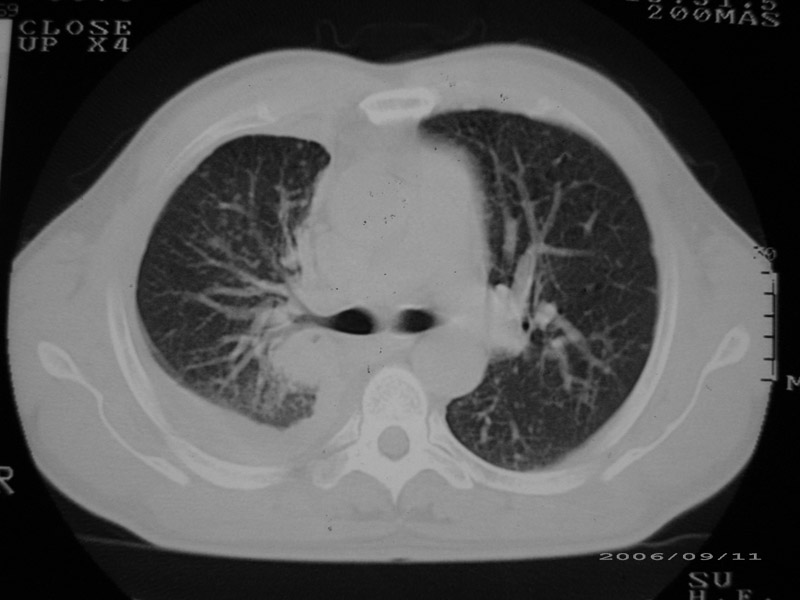

以下是引用守望可可西里在2006-9-11 15:29:00的发言:[br][br] ct平扫表现:右侧胸膜腔缩小,积液,胸膜增厚且不均匀、不规则,以纵隔胸膜增厚为主,边缘呈锯齿状,并见附壁内突之结节状肿块影。右肺含气量减少,纹理聚集,右肺门中下部见数个肿大的淋巴结。纵隔无移位,内未见明显肿大淋巴结,双侧主支气管以及各叶、段支气管比较通畅。。[br] 考虑:右侧胸膜恶性间皮瘤,伴肺门淋巴结转移。